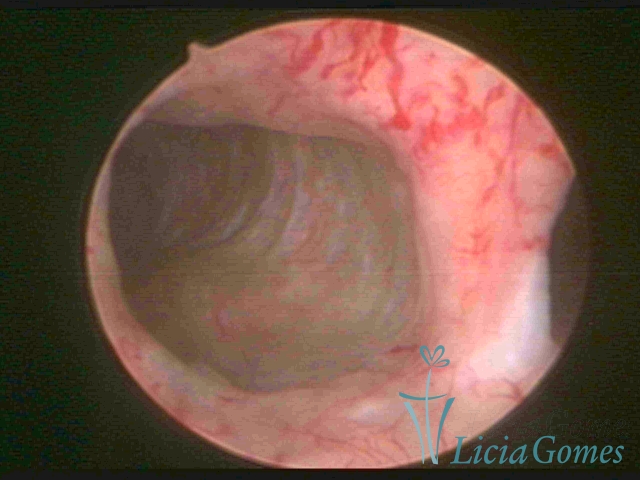

Uterus didelphys

The presence of two uterine cervices and a double vagina, similar to unicornuate uteri, with a normal covering of endometrium.